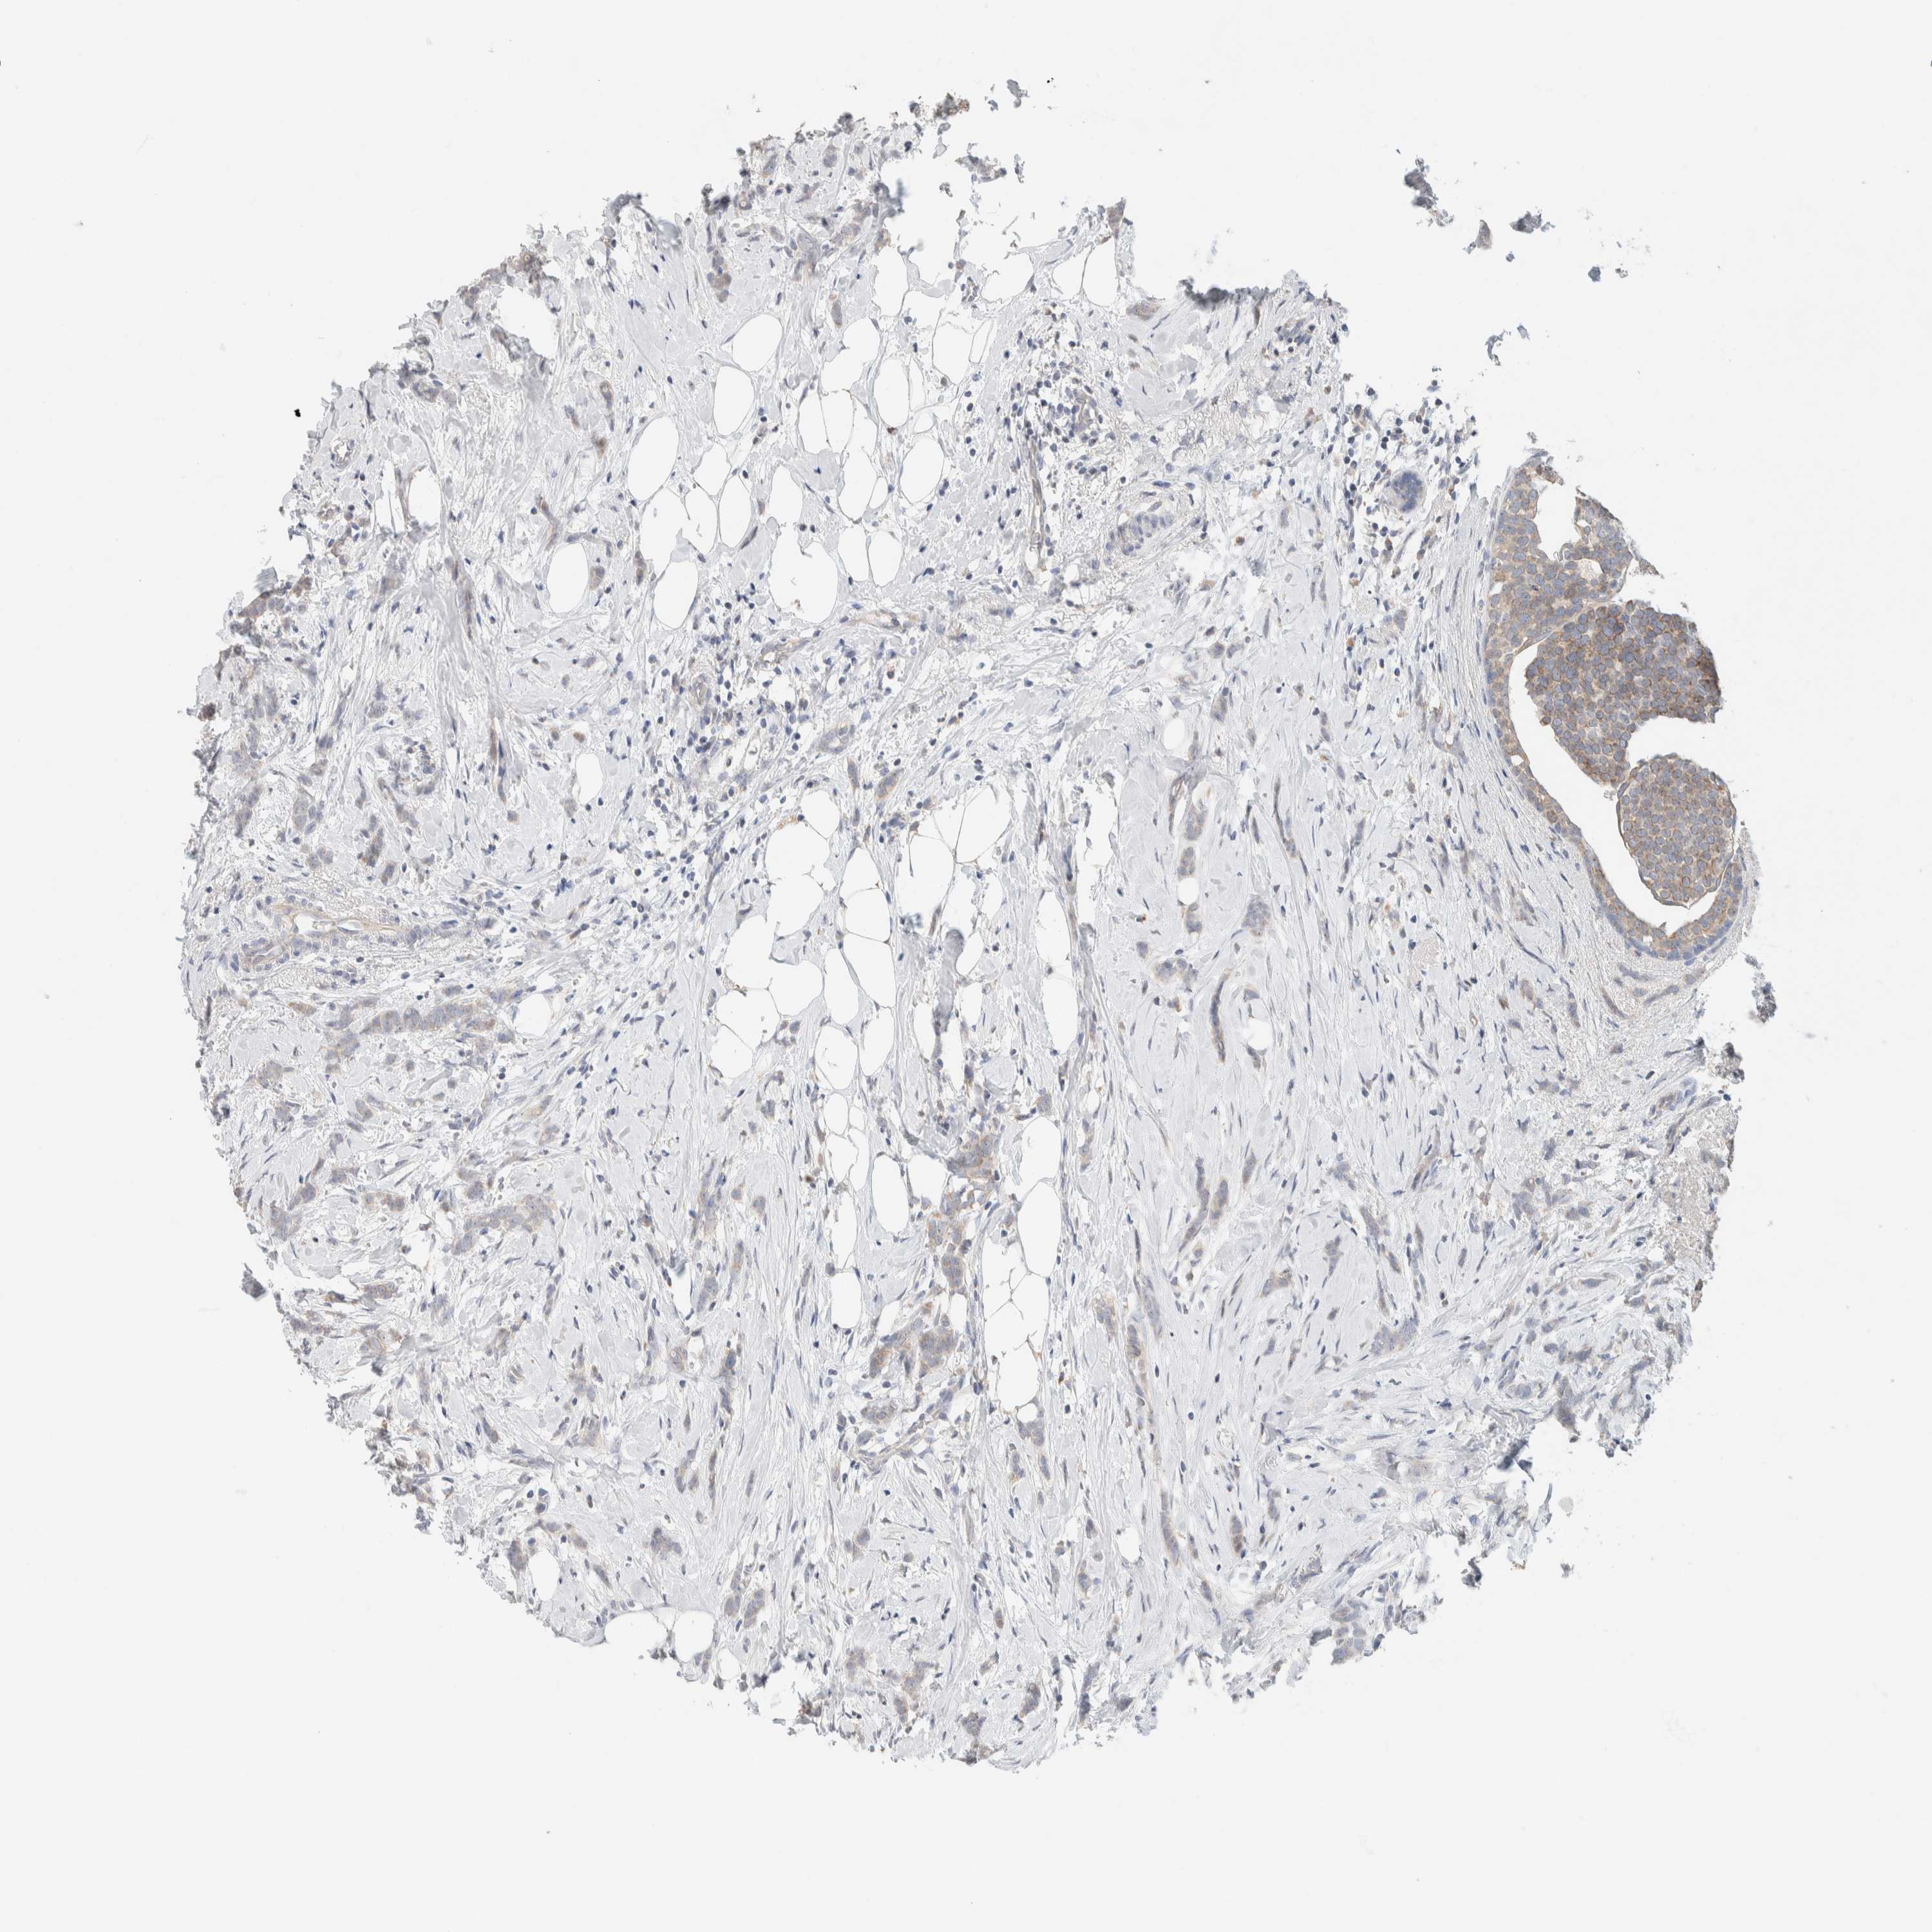

CANCER BREAST CANCER Show tissue menu

BRCA TCGA BRCA VALIDATION PROTEIN EXPRESSION